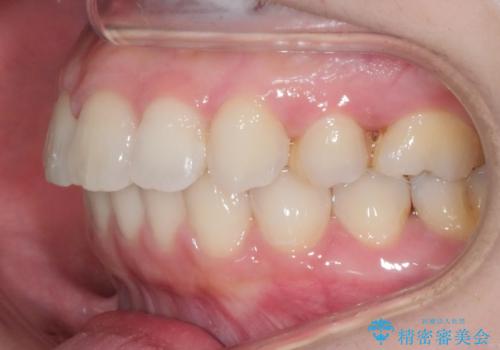

後戻りの程度としては軽度なので、治療期間としては短く終えることが出来ました。

前歯の正中線も改善され大変満足して頂きました。